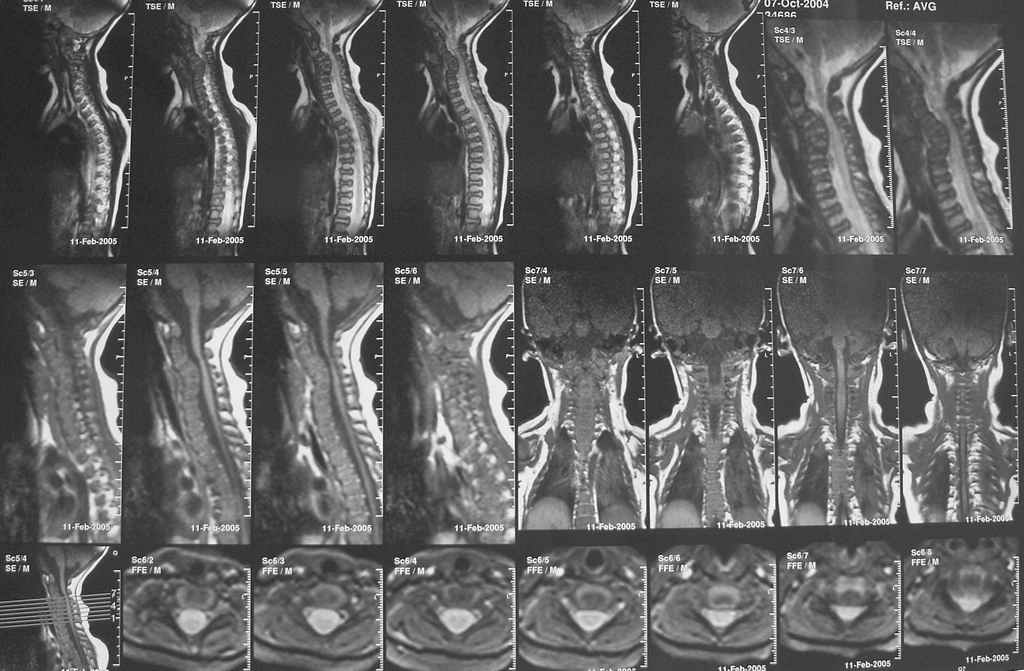

Девочка 5 месяцев, дочь коллеги, врача-анестезиолога, тетрапарез, в ногах спастический в руках - вялый, усугубившийся после "мануальной терапии".

Данные рентгена,КТ и МРТ прилагаются. Кроме того, имеется двухсторонний врожденный вывих бедра. По совокупности данных - болезнь Ларсена. В шейном отделе - дисплазия и гипоплазия суставных отростков С3-С5 с передним подвывихом и антелистезом, патологическим кифозом и стенозом позвоночного канала до 55% от исходного (5 мм при исходном 9 мм). Spina bifida occulta в 5 сегментах, в том числе расщепление задней дуги атланта, агенезия его передней дуги. Признаки спинальной компрессии и диффузной миелопатии на уровне стеноза. Вопрос - возможно ли в таком нежном возрасте оперативное лечение и вообще, какая должна быть тактика ?